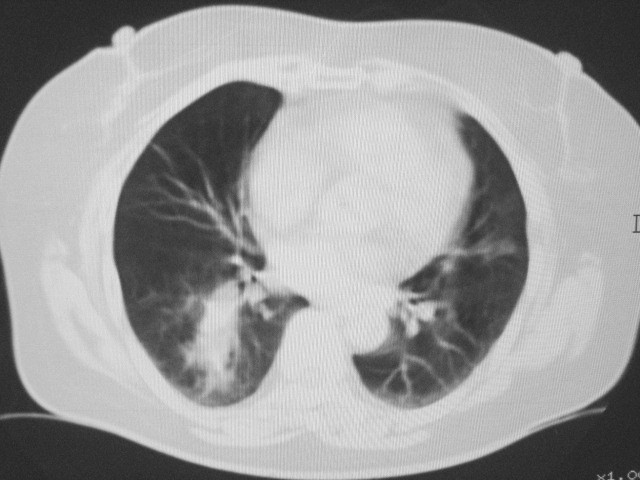

以下是引用清清楚楚在2007-8-28 7:13:00的发言:[br]右肺下叶可见斑片状高密度影,边缘模糊;右肺中叶内侧段及左肺舌段亦可见小斑片状模糊影。[br]考虑双肺感染,建议抗炎治疗后复查。

以下是引用天南地北在2007-8-27 23:49:00的发言:[br]右肺下叶可见斑片状高密度影,边缘模糊;右肺中叶内侧段及左肺舌段亦可见小斑片状模糊影。[br]考虑双肺感染,建议积极抗炎治疗后复查。

以下是引用天南地北在2007-8-27 23:49:00的发言:[br]右肺下叶可见斑片状高密度影,边缘模糊;右肺中叶内侧段及左肺舌段亦可见小斑片状模糊影。[br]考虑双肺感染,建议抗炎治疗后复查。

以下是引用难听在2007-8-28 13:17:00的发言:[br]右肺下叶背段支气管狭窄,是否可以考虑新生物伴阻塞性肺炎.请大家帮帮忙,这个病人是卫生局长的丈母娘.惹不起啊.